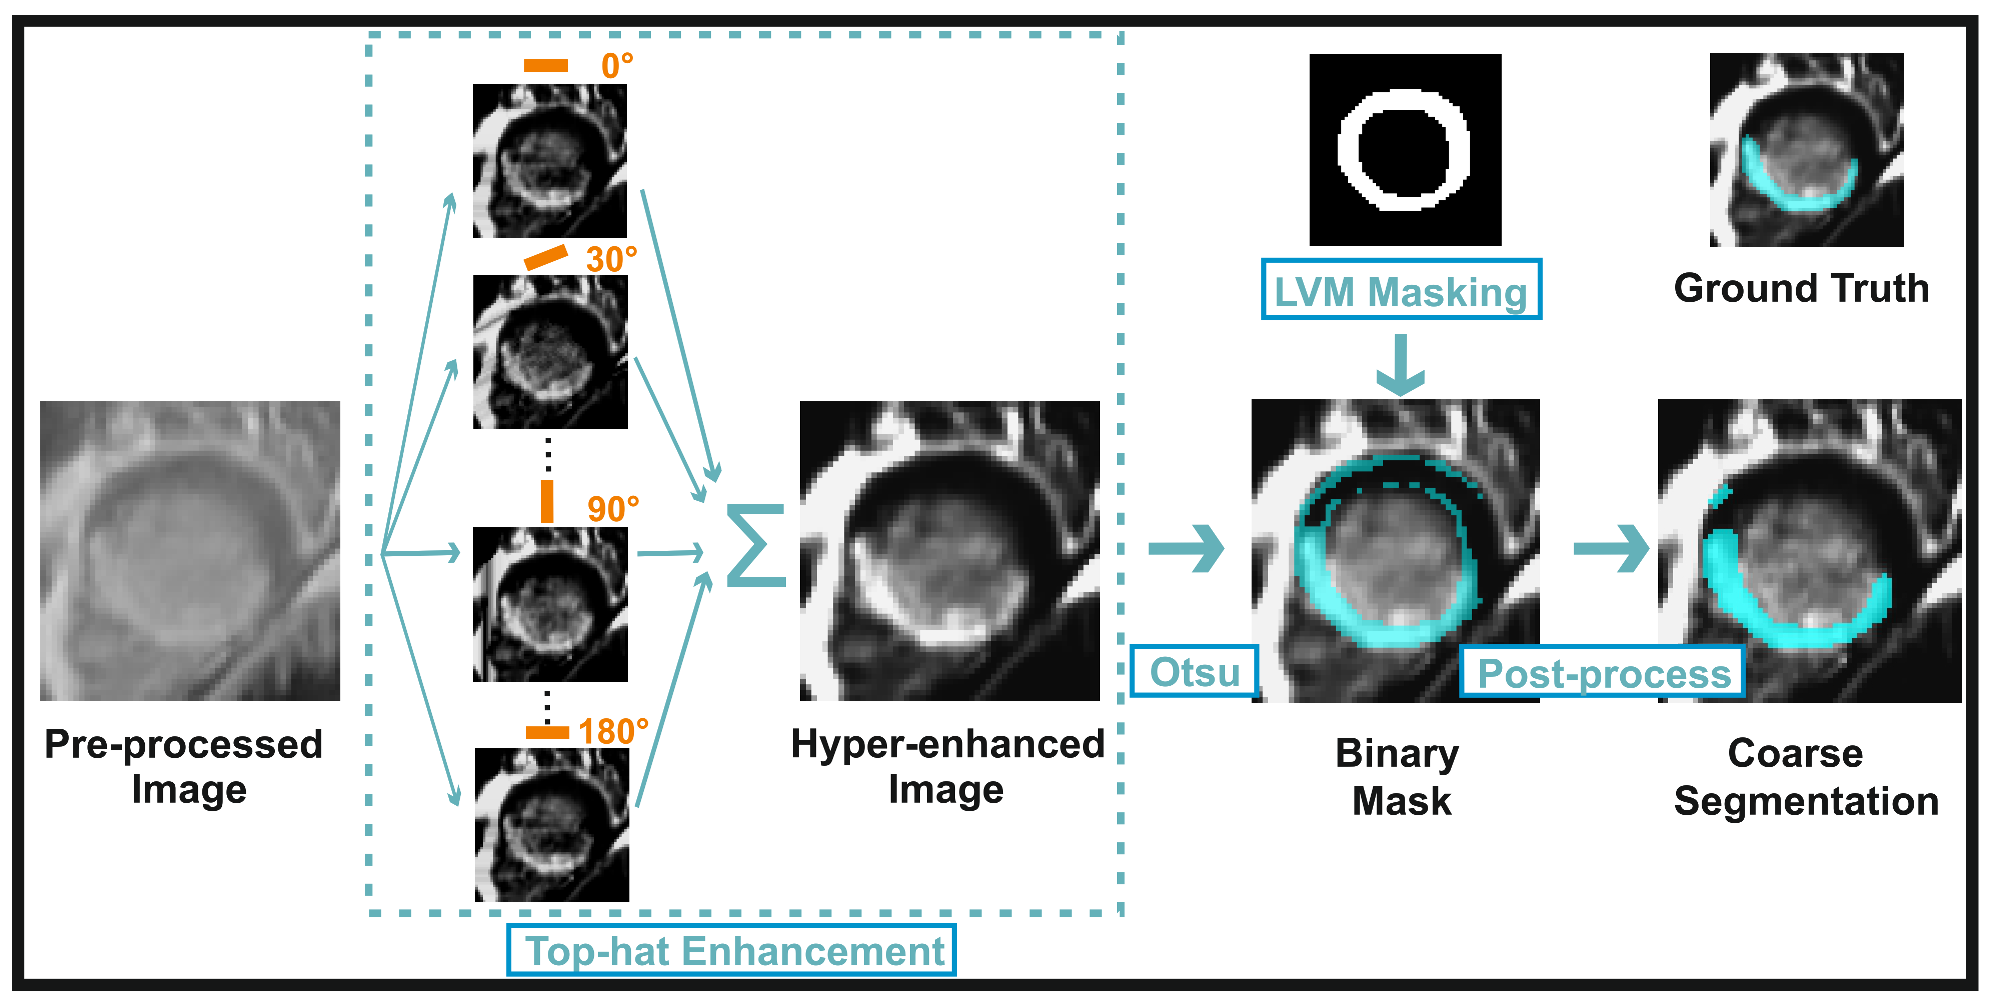

3.2.3. Myocardial Scar Quantification: Coarse Segmentation

3.2.4. Myocardial Scar Quantification: Refined Segmentation